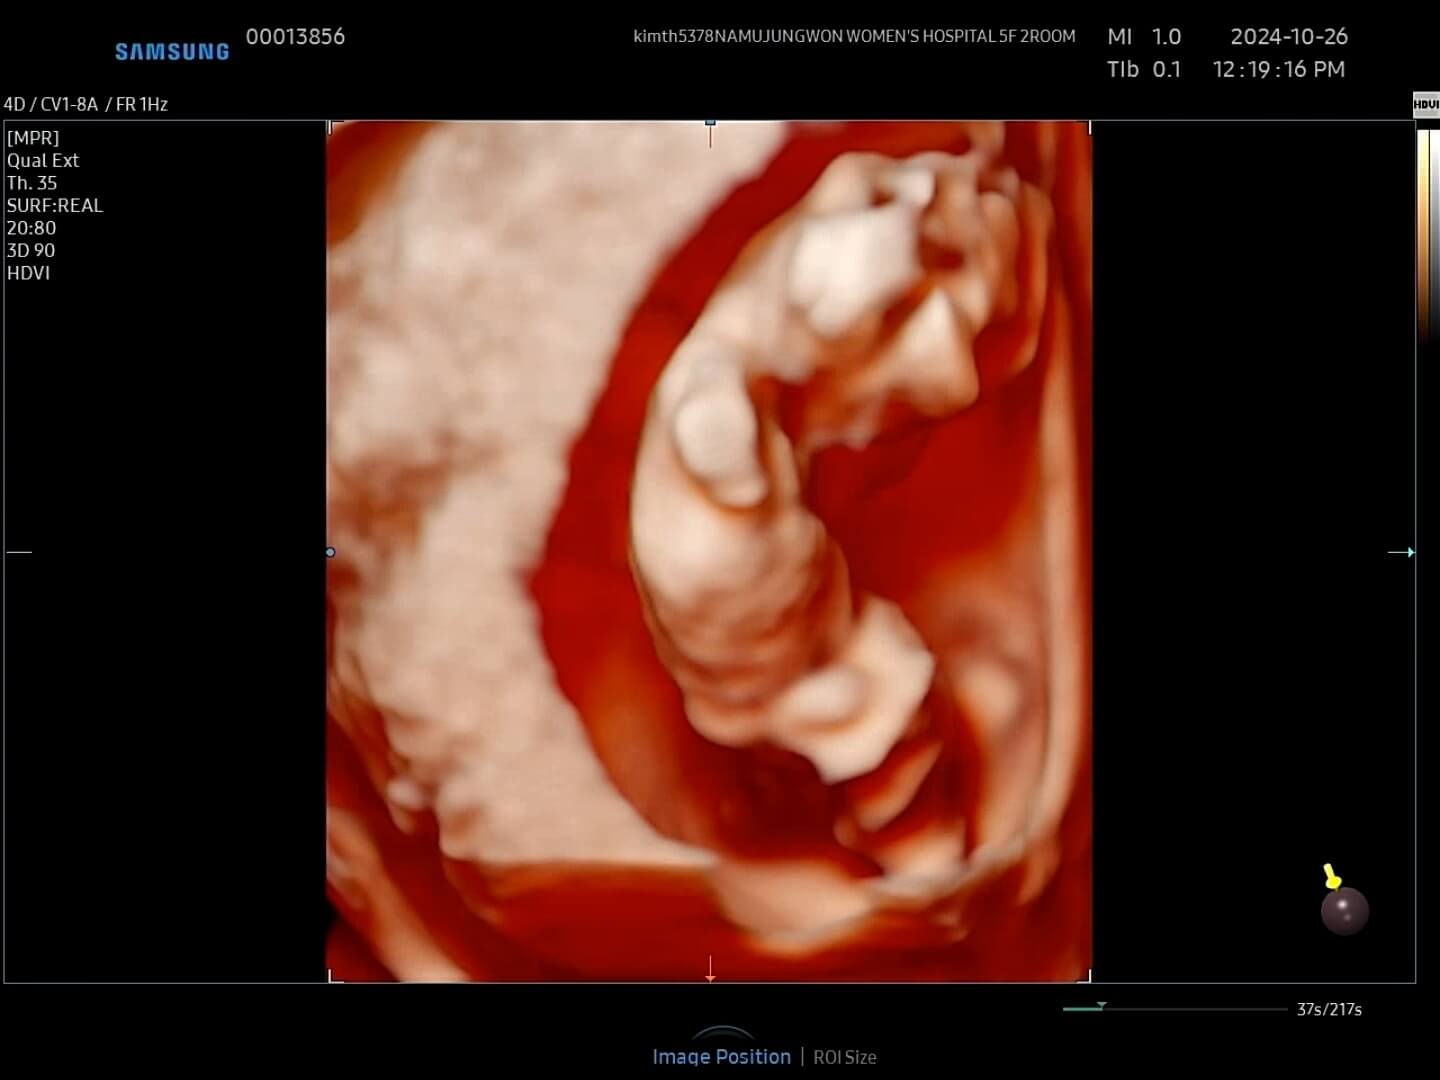

4. 12주 입체초음파

드디어 12주가 되어 꾸미의 첫 입체초음파를 보는 날이 되었어요! 두근두근, 꾸미는 얼마나 커있을까요?

12주-입체초음파 12주에는 첫 입체초음파를 보게 되면서 팔, 다리가 잘 형성되었는지 정도를 보는 것 같아요. 12주부터 '태아'라고 부르기도 한답니다. 우리 꾸미는 처음에는 등을 돌리고 있다가 서서히 얼굴을 보여줬습니다. 벌써부터 귀여워요! 아들인지 딸인지 너무 궁금했는데요, 성별은 입체 초음파가 아닌 일반 초음파로 봐야한다고 하셨어요.